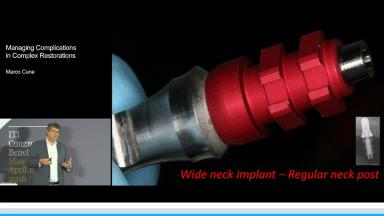

Managing Complications in Complex Restorations

This lecture discusses a wide variety of complications with prosthetic procedures. Possible causes of these complications are outlined, ranging from treatment planning to dental laboratory issues. This presentation highlights problems of poor technical decision-making and execution as well as engineering and component failures. Clinical cases with advanced and complex prosthetic failures are presented to illustrate different scenarios and situations that can occur when planning and placing implant-supported prostheses.